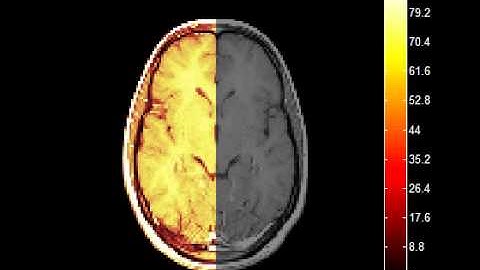

Image Reconstruction for Magnetic Resonance Imaging (MRI) using MATLAB | MATLABSolutions